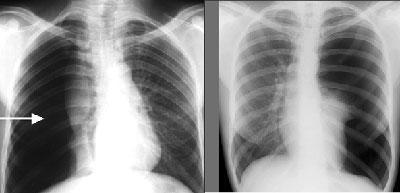

Чтобы подтвердить диагноз, больного направляют на рентгенологическое обследование. На снимке специалист может заметить светлую зону в стороне поражения, на этом участке отсутствует лёгочный рисунок. Зона поражения отделена чёткой границей от спавшегося лёгкого.